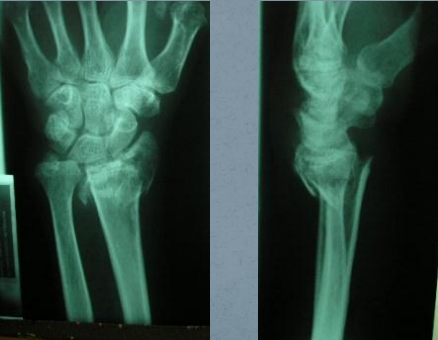

- Raio X de Punho: Ap e Perfil

- No Ap: Avaliamos:

– Comprimento do Rádio Distal

– Articulação Rádio-Escafóide

– Articulação Rádio-Semilunar

– Articulação Radioulnar Distal

– Osso do Carpo

o No Perfil: Avaliamos:

– Desvios ósseos do rádio distal

– Luxação Radioulnar distal

– Luxações dos ossos do Carpo

– Luxações das articulações carpos-metacarpais

– No Raio X: Avaliamos a qualidade do tecido ósseo